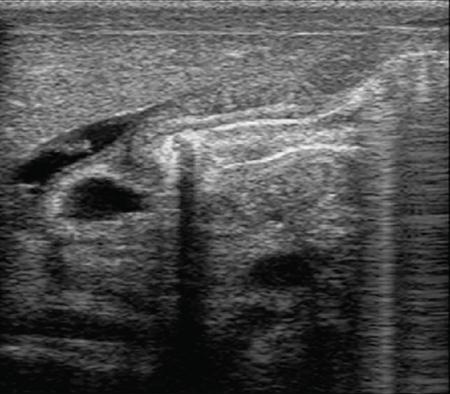

Rashmi Dixit, Anju Garg Abdominal masses are a common clinical problem in children, arising from virtually any abdominal organ. Masses arising from the gastrointestinal (GI) tract are not uncommon. They may be congenital or developmental, inflammatory, infective, idiopathic or neoplastic in nature. A high index of suspicion is necessary so as to ensure an early diagnosis and appropriate management. Imaging, therefore, plays a vital role in identifying the location, nature and extent of the mass lesion. Ultrasound (US) is the first-line imaging method for GI masses, like for most paediatric abdominal masses. It does not require sedation and is nonionizing which are important considerations in the paediatric population. US findings may be diagnostic in certain masses when no further imaging is required. Computed tomography (CT) plays an important role in complete evaluation of GI masses especially where US is either not diagnostic or the full extent and nature of the mass needs to be delineated, especially prior to surgery. It requires the administration of intravenous contrast and preferably oral contrast as well. Sedation may be required and it carries the risk of radiation exposure. Each study, hence, needs to be tailored to answer the clinical question at hand, while ensuring the lowest possible radiation exposure. Magnetic resonance imaging (MRI) provides excellent contrast resolution, which along with its nonionizing nature makes it a very attractive imaging technique. However, due to the relatively long imaging time requiring sedation, sensitivity to motion both respiratory and bowel and limited availability it is generally used as a problem-solving tool. Plain films and contrast studies currently have a very limited role in the evaluation of GI masses. Plain films may be diagnostic in masses like teratomas, while contrast studies may be required for mucosal abnormalities and small endoluminal masses like polyps. Enteric duplication cysts can occur along any portion of the GI tract from the pharynx to the rectum. They are found most often in the ileum (33%). The other sites are the oesophagus (20%), colon (13%), jejunum (10%), stomach (7%) and duodenum (5%). The incidence is reported to be around 0.2% of all children, with a slight male predominance. Duplication cysts are thought to arise between the 4th and 8th weeks of development; however, their aetiology is unknown and several different theories have been proposed. In 16%–26% cases there may be associated spinal defects, cardiac or urinary malformations. Other associated GI anomalies may be seen in about 10% of cases. Duplication cysts typically lie along the mesenteric border of the gut. They have smooth muscle wall which they share with the adjacent gut, as also the blood supply. On histopathology, three classical features are seen: an epithelial lining with GI mucosa, a smooth muscle covering and a close attachment to the GI tract due to a shared common wall. Although the mucosal lining does not necessarily match with the adjacent portion of the gut, nonetheless, duplications are named after the portion of the gut to which these are closely related. About 20%–30% of these duplication cysts contain ectopic gastric mucosa which is more common in oesophageal and small intestinal duplication cysts. Ectopic pancreatic mucosa may also be seen, most often in gastric duplication cysts. Morphologically they may be cystic or tubular with the former accounting for 80% and the latter for 20%. While cystic duplications mostly do not communicate with the adjacent gut, tubular duplications that run parallel to the GIT often do, hence in these cases connection with GIT must be demonstrated for operative planning. Duplication cysts may be multiple in 1%–7% of cases usually occurring in the same segment of the GIT. An atypical duplication cyst is an isolated duplication cyst which is completely separated from the GIT and has no communication or shared wall with the gut. They are extremely rare and thought to be the result of a vascular injury. Although duplication cysts may remain asymptomatic till adulthood they mostly present within the first year (70%). Almost 85% present by the second year. Clinical features depend not only on the size and location, but also on the presence of any ectopic mucosa and complications. Pharyngeal and oesophageal cysts may present with respiratory distress or dysphagia. Infection and rapid growth may cause retrosternal pain or haemoptysis. Gastric and intestinal duplications cause nonspecific symptoms like recurrent abdominal pain nausea, vomiting, distention or a palpable lump. High pressure inside the cyst consequent to accumulation of secretions is thought to be responsible for the recurrent abdominal pain. Obstruction due to intussusception or extrinsic compression may occur. Presence of gastric mucosa is associated with complications like inflammation, bleeding, ulceration and perforation. US is most useful for the diagnosis of abdominal duplication cysts and sometimes may demonstrate these on an antenatal scan. MR and CT are mainly used for oesophageal duplication and for planning surgery. Endoscopic trans oesophageal ultrasound may be informative for oesophageal duplications but is not a part of routine practice. Classical US features in uncomplicated duplication cysts include: a unilocular cystic structure in close proximity to the bowel. The cyst has a relatively thick wall which has a hyperechoic inner lining representing the mucosa and an outer hypoechoic rim produced by the smooth muscle layer (muscularis propria) – the so-called ‘gut signature’ sign. This sign is also referred to as the ‘double-wall’ or ‘muscular rim’ sign. (Fig. 7.7.1) Though, most characteristically described for duplication cysts, it may sometimes be seen in some other cystic lesions such as a complicated mesenteric cyst, Meckel’s diverticulum or torsed ovarian cyst. Some US signs described recently are: the ‘five layered cyst wall sign’ and ‘Y configuration of the muscle wall sign’. It has been shown that with the use of high frequency US transducers (12–18 MHz) the wall of the duplication cyst can demonstrate the same five layered wall structure as the normal GIT. From inside to outside these are: the innermost mucosa which is hyperechoic, muscularis mucosa (hypoechoic), hyperechoic submucosa, hypoechoic muscularis propria and the outermost serosa which is hyperechoic. If all these five layers can be identified in a cyst it is diagnostic of an enteric duplication cyst; however, the sign is difficult to demonstrate (Fig. 7.7.2A and B). The second sign arises because a duplication cyst shares its wall with the adjacent gut. Splitting of the common muscularis propria between the cyst and the adjoining bowel loop results in the Y configuration of the muscle layer on US, reflecting one of its important histological features. When this is seen, it is possible to confidently diagnose an enteric duplication cyst as this sign has not been demonstrated in other cysts. The ‘Y configuration sign’ can be particularly valuable in complicated cysts In addition, since US is a real time examination it also allows visualization of peristalsis of the cyst wall which is seen as a transient change in the cyst shape and contour due to contraction of the cyst wall (Fig. 7.7.3A and B). This requires the transducer to be kept stationary over the cyst for some time Most duplication cysts are anechoic but some echoes due to mucinous fluid or septations can be seen at times, and do not imply complications. Complications include haemorrhage (due to ectopic gastric mucosa), enzymatic destruction of the mucosal lining, inflammation (due to ectopic pancreatic tissue) and infection. In these cases, fluid levels or echogenic debris can be seen within the cyst with a thick hypervascular wall which may lack layers (see Fig. 7.7.2B). In these cases, the Y configuration sign can help to suggest the correct diagnosis. The inflammatory changes may extend to the surrounding mesenteric fat as well, which becomes hyperechoic. Duplication cysts near the ileocecal valve, can act as a lead point for intussusception. Atypical or isolated duplication cysts, may just produce the pseudokidney sign. The important US features of duplication cysts are listed in Box 7.7.1. Key Ultrasound Signs of Duplication Cysts CT is not performed for the diagnosis of duplication cysts, however, it can demonstrate the location, anatomical relationships, exact extent and the associated anomalies. On CT evaluation a cystic mass closely related to the adjoining GI wall is seen. The wall shows mild enhancement. A complicated duplication cyst showing internal high attenuation, air foci, thick enhancing wall and surrounding inflammation suggests infection (Fig. 7.7.4A and B). Internal high attenuation alone, however, could be due to proteinaceous contents or haemorrhage and does not imply infection on its own. MR is also not generally used as a diagnostic tool due to long examination times requiring sedation but is especially useful to demonstrate the cystic nature of thoracic duplications. Duplications cysts show hypointense signal on T1W sequences and very high signal on T2W images. Both CT and MR may be used prior to surgery. MR may have an additional value in assessment of foetal abdominal cysts. Differential diagnosis includes other cystic lesions such as mesenteric, omental, ovarian and choledochal cysts. In patients with an antenatal diagnosis, although the optimal time for resection is not defined, it is suggested that early resection within the first 6 months be considered. Treatment of asymptomatic duplication cysts remains controversial, however, since early elective surgery is associated with less morbidity and a shorter hospital stay than excision in symptomatic cases, it should be preferred. In addition, complications such as obstruction or massive bleeding may be life threatening and there is a potential risk for malignant transformation in adults. The cyst can be removed alone, but if there is a communication with the adjoining gut its resection will be required. Currently, minimally invasive surgery is becoming the procedure of choice. Complete excision is important to avoid cyst recurrence or subsequent malignant changes. Hypertrophic pyloric stenosis was earlier believed to be a developmental anomaly but is currently thought to be acquired disorder. It is characterized by hypertrophy of the circular muscle layer of the pylorus. This results in thickening and lengthening of the pylorus ultimately progressing to gastric outlet obstruction. The etiopathogenesis of this disorder is unknown but postulated mechanisms include abnormal innervation of the pylorus and duodenal irritation due to hypersecretion. Various genetic and environmental factors such as maternal smoking and use of erythromycin have also been implicated. Several ultrastructural anomalies have been identified in the muscle layer including abnormal nerve endings, decreased synthesis of nitric oxide, reduction in the number of cells of Cajal and an increased production of insulin-like growth factors. These factors are thought to cause muscle hypertrophy and failure of muscle relaxation. The incidence of HPS is about 3 per 1000 live births with male to female ratio of 4–5:1. Patients usually present between 2 and 6 weeks of age. The child is typically normal at birth and, subsequently develops non-bilious vomiting around 2–3 weeks of age. There may be a small lump palpable in the epigastrium, the so called ‘pyloric olive’, in nearly 80% of cases. Also, peristalsis may be seen traversing the epigastrium. If vomiting persists, dehydration and hypochloraemic alkalosis can develop. In the presence of a classical history and examination findings, the diagnosis is often made clinically and imaging is only used to confirm the diagnosis. US allows visualization of the pyloric canal morphology as well as behaviour during dynamic evaluation. Ultrasonography is performed with a high-frequency transducer ranging between 6 and 15 MHz. The child is placed supine and the examination is best performed with a moderately fluid-filled stomach. The first step is to localize the gallbladder as the pylorus lies posteromedial to the gallbladder. Another useful trick is to first localize the upper pole of the right kidney and then move the transducer medially towards the xiphoid to identify the pylorus. The transducer is then angulated so that the pyloric canal is well visualized in long axis. Correct positioning so that the pyloric canal is seen as a straight line is important to ensure that measurements are not performed in a tangential plane which can result in fallacious increase in muscle thickness. Sometimes a gas distended stomach may preclude visualization of the pylorus. In this case, shifting the child to an oblique position so that the right side is placed inferiorly allows fluid to move into the antrum which acts as an acoustic window. A markedly distended stomach can displace the pylorus posteriorly making it difficult to visualize. In this situation moving the child so that the left side is down or prone positioning may help localize the pylorus. Distention of the stomach with water rather than milk may be a better option as milk may at times also cause artefacts. A nasogastric tube may be used to fill up the stomach when necessary. The most important diagnostic feature of HPS is thickening of the muscle layer of the pylorus seen as hypoechoic curved bundles between the antrum and duodenal cap. A number of signs that have been described on sonography in HPS include the ‘empty cervix’ sign as the hypertrophied muscle mass indents the fluid filled antrum and duodenal bulb mimicking the appearance of cervix in longitudinal section (Fig. 7.7.5). The hypertrophied pylorus gives appearance of a ‘doughnut or a target’ in transverse section. The ‘antral nipple’ or ‘mucosal nipple sign’ refers to redundant pyloric canal mucosa protruding into the antrum. This can be seen as an echogenic structure protruding into the fluid filled antrum (Fig. 7.7.6). The fluid trapped between the mucosal folds in the centre of an elongated pylorus may be seen as two sonolucent lines in the centre referred to as the ‘double track sign’. Measurement of muscle layer thickness provides objective assessment of pyloric thickening. A muscle layer thickness of more than 3 mm is considered abnormal. This should be measured from the outer echogenic edge of the mucosa to the outer edge of the muscle on both transverse and longitudinal scans. A muscle wall thickness of less than 2 mm is considered normal while a thickness between 2 and 3 mm is considered equivocal as it can be seen in other conditions like pylorospasm or gastritis besides HPS. Pyloric canal length of less than 14 mm is thought to be unequivocally normal. A pyloric canal length of more than 15–17 mm is also considered diagnostic for HPS (Fig. 7.7.6). However, the measurement of canal length is much more difficult to perform and subject to variability, hence this should not be used alone to make the diagnosis of HPS. Total diameter of the pylorus over 13 mm and pyloric volume measurements have also been suggested, but muscle thickness measurement remains the most accurate In addition, real-time observation of the pyloric behaviour is also important. The stomach tends to be markedly distended and shows increased peristalsis with failure of gastric contents to pass into the duodenum. The other hand a wide-open pylorus with normal passage of contents into the duodenum excludes the diagnosis of HPS (Box 7.7.2). Key Ultrasound Features of Hypertrophic Pyloric Stenosis There is a higher incidence of renal anomalies in these patients and hence kidneys should be examined once diagnosis is established. Pitfalls in sonographic diagnosis include non-visualization of the pylorus due to an overdistended stomach pushing it posteriorly, tangential views of the pylorus or pylorus spasm producing a pseudo thickening of the pylorus. Hence it is important to make sure that the pylorus is correctly imaged and the entire pyloric length is visualized in longitudinal plane. As opposed to pylorus spasm the thickening and the appearance of pylorus in HPS tends to persist, while pylorospasm is transient and generally resolves within 30 minutes. If the muscle layer measures 2–3 mm in thickness and the pylorus does not relax during the US examination clinical follow up and repeat US examination may be advisable. Borderline measurements are more likely to occur in preterm infants. Some authors have provided measurements of the pyloric length and muscle thickness correlated with the age and weight of the child which may be helpful in small and premature patients. In equivocal cases, it is preferable to perform a repeat examination rather than erroneously make a false-positive diagnosis, as HPS is not a surgical emergency. A barium study may be performed if the US examination is inconclusive. Use of a nasogastric tube is preferred as it allows a controlled filling of the stomach with barium. The upper GI barium study shows delayed emptying of the stomach. The pyloric canal is elongated and narrowed visualized as a curved streak of barium directed upwards and posteriorly, referred to as the ‘string sign’. This combination of narrowed pyloric canal along with elongation is the most important feature of HPS on contrast studies. A ‘double string sign’ is produced when barium is caught between the folds of mucosa overlying the hypertrophied muscle. ‘Antral beaking’ refers to a mass impression upon the antrum with a streak of barium entering the narrowed pyloric canal. The hypertrophied muscle may indent the gastric antrum as well as the duodenal bulb producing the ‘shoulder sign’. Disruption of the antral peristalsis may result in a small outpouching along the lesser curvature of stomach producing the ‘pyloric teat’ sign. The stomach shows hyperperistalsis on fluoroscopic examination which is sometimes referred to as the ‘caterpillar sign’ (Box 7.7.3). These signs may sometimes be seen in pylorospasm but are not persistent. Therefore, it is important that the study is of sufficient duration to establish the persistence of findings. Any the residual barium must be aspirated if a nasogastric tube has been placed, in order to avoid aspiration. Key Upper GI Features of Hypertrophic Pyloric Stenosis The treatment of HPS is surgical, that is, Ramstedt’s pyloromyotomy. Postoperatively, in the first week, the muscles may remain same in thickness or even thicker than that prior to surgery. The muscle thickness gradually returns to normal with the anterior part of the muscle normalising first followed by the posterior portion. The anterior portion usually returns to a thickness of 3 mm within 3 months whereas the posterior portion may take up to 5 months to normalize. This is related to the usual anterior surgical approach. The gastric emptying, however, returns to normal within 2–3 days. An upper GI examination may also be used to assess gastric emptying postoperatively and to exclude gastro-oesophageal reflux if vomiting persists. GI polyps are commonly seen in childhood between 2 and 5 years of age and are the most common cause of painless rectal bleeding in children. Juvenile polyps are the most common type of polyps that are seen in children accounting for about 80% of the polyps. The term juvenile refers to the histology of the polyp rather than the age at which they occur. Histologically these lesions represent benign hamartomas. Diagnosis is made via rectal examination or sigmoidoscopy. Radiological examination is rarely required for diagnosis. Polyps in the distal colon and rectum can be easily resected via endoscopic polypectomy. Inflammatory polyps are commonly seen in children with inflammatory bowel disease. Most of these polyps are actually pseudo polyps formed by hyperplastic and inflamed mucosa in areas of inflammation and mucosal injury. They may reach large sizes but are not pre-malignant. Imaging reveals evidence of inflammatory bowel disease along with polyps. Juvenile polyposis syndrome is an inherited condition characterized by multiple juvenile polyps. The following criteria must be met for diagnosis of JPS (a) more than 5 juvenile polyps in the colon or rectum (b) juvenile polyps in other portions of the GI tract (c) any number of juvenile polyps with a positive family history. Single juvenile polyps are not a feature of juvenile polyposis syndrome. JPS has been categorized into 3 types depending on the clinical features and age of onset. Diffuse juvenile polyposis of infancy presenting in children up to 3 months of age. generalized juvenile polyposis with polyps throughout the GIT and juvenile polyposis coli (JPC) with polyps only in the colon beginning in children and adolescents. Children can present with diarrhoea, rectal bleeding, intussusceptions or anaemia. The diagnosis is usually established by colonoscopy. Double-contrast barium enema or CT colonogram can also demonstrate multiple polyps within the colon. Peutz-Jeghers syndrome is rare autosomal dominant disorder characterized by hamartomatous polyps throughout the GI tract. Mutation of ATK tumour suppressor gene is seen in some cases. Histologically these polyps are characterized by a smooth muscle core arising from the muscularis mucosa. Although polyps occur anywhere in the GI tract, they are commonest in the small bowel. They can be sessile or pedunculated and being firm in nature (due to the smooth muscle core) are particularly prone to intussusception. They may also present as GI bleed and anaemia Although the polyps of PJS are benign hamartomas the syndrome is associated with an increased risk of malignancy (adenocarcinoma). The diagnosis of PJS can be made if there are 2 or more histologically confirmed PJS polyps, any number of PJS polyps along with the typical mucocutaneous pigmentation, a family history of PJS with any number of PJS polyps or the presence of mucocutaneous pigmentation with family history of PJS. Because of the presence of small bowel polyps CT enterography, MR enterography and small bowel enema also have an important role to play in the diagnosis. The polyps are seen as sessile or pedunculated intraluminal filling defects on these studies. They may also be seen as the lead point of an intussusception (Fig. 7.7.7). Endoscopy and colonoscopy are used to establish the diagnosis. Video capsule endoscopy is especially useful to identify the polyp burden in the small bowel. The treatment is aimed at removing the larger polyps either surgically or endoscopically so as to avoid obstruction.